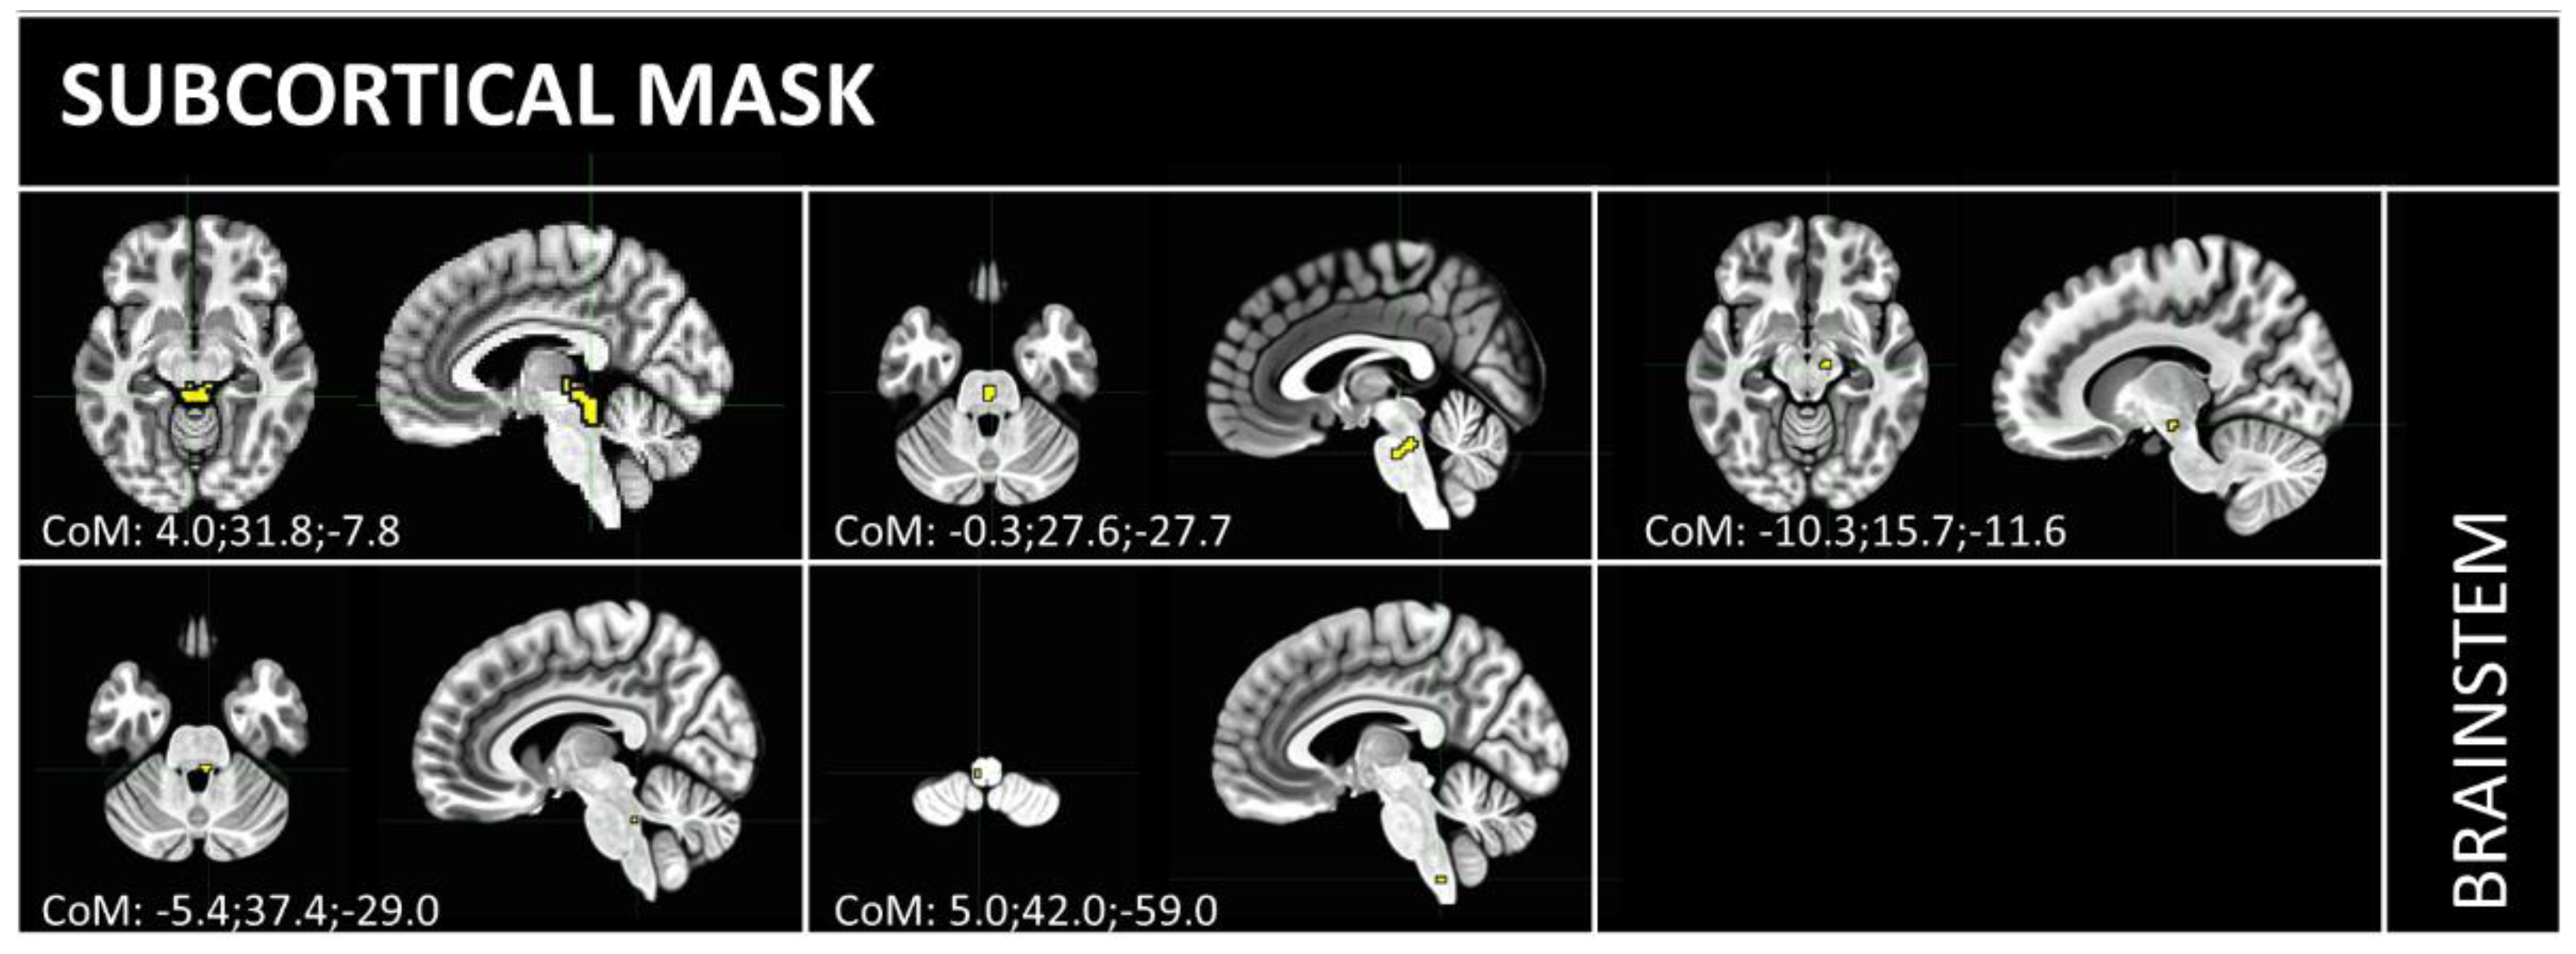

| Global Mask | Subcortical Mask | ||||

|---|---|---|---|---|---|

| 3–7% (ρ) | 3–0% (ρ) | 7–0% (ρ) | 3–7% (ρ) | 3–0% (ρ) | 7–0% (ρ) |

| 4–2 (0.73) | 1–1 (0.66) | 2–2 (0.76) | 1–3 (0.72) | 1–3 (0.65) | 3–3 (0.69) |

| 11–5 (0.65) | 4–2 (0.69) | 5–10 (0.57) | 6–2 (0.60) | 2–1 (0.59) | 5–1 (0.61) |

| 17–18 (0.64) 1 | 11–10 (0.60) | 18–19 (0.58) 1 | 2–5 (0.64) | 4–8 (0.58) 2 | 7–8 (0.60) 2 |

| 20–20 (0.54) | 17–19 (0.73) 1 | 20–20 (0.52) | 4–7 (0.75) 2 | 6–4 (0.59) | 2–4 (0.57) |

| 9–9 (0.51) | |||||